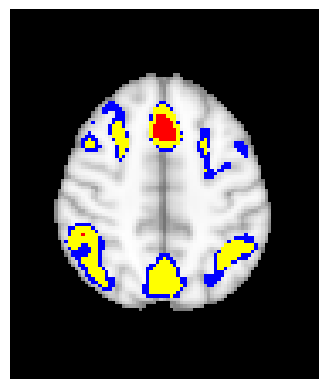

The confidence regions are constructed on fMRI scans from 77 subjects as a real data application of the proposed methods after applying additional smoothing with Gaussian kernel with FWHM to match the results shown in Bowring (2019) [BOWRING2019116187]. Confidence regions using 1) the joint method with , 2) the separate method with BH adjustment for upper and lower side each with , 3) the separate method with BH adjustment for upper side and two-stage adaptive procedure for lower with , and 4) SSS () were compared with threshold level 1.0%, 1.5%, and 2.0% Blood Oxygenation Level Dependent (BOLD) change. Joint control confidence regions are produced with instead of 0.05 for the reasons mentioned in chapter 3.

For all slices, FDR controlling methods show tighter inference of both upper and lower CR compared to the SSS method. SSS shows smaller upper CR and larger lower CR which suggests more conservative inference compared to FDR controlling testing based methodologies. This is due to the fact that by controlling for FDR, the method allows for more false discoveries in exchange for more discoveries in general. Despite having higher level at , joint control confidence regions still show comparable results to other methods even with higher significance level. Naturally, as the threshold goes up, the area enclosed between the upper and lower confidence regions decreases.

Confidence regions with separate controls of FDR for lower and upper are presented in two forms for comparison: one with BH procedure for the lower confidence region, and the other one with the two-stage adaptive procedure for the lower confidence region. The upper confidence region remains the same as both methods uses BH procedure for the upper set FDR control. Lower confidence regions with adaptive method are smaller than lower sets with BH procedure which is to be expected as the two-stage adaptive procedure is less conservative when more voxels are thought to be rejected. In the context of negative one-sided testing, this is equivalent to when there are less number of voxels above than below .